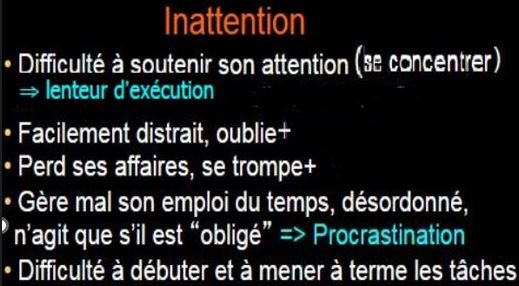

Type inattentif

C’est la base de ce trouble et c’est plus une inconsistance de

l’attention qu’un déficit d’attention. Ce

sous-type concerne un peu plus les jeunes filles et les femmes.

– Ceux qui ont uniquement cette

composante sont des rêveurs et passent

d’une idée à l’autre, souvent sans les mettre en action et donc en

commençant peu d’actions.

– Distraits, étourdis, démotivés

chroniques, indécis, capable d’hyperfocaliser aussi, ils ne sont

pas souvent diagnostiqués TDAH, car ils ne dérangent pas leur entourage

et sont à l’opposé de l’hyperactivité au niveau comportemental.

– Ils

sont au contraire hypoactifs et peuvent même sembler apathiques aux yeux

des autres.